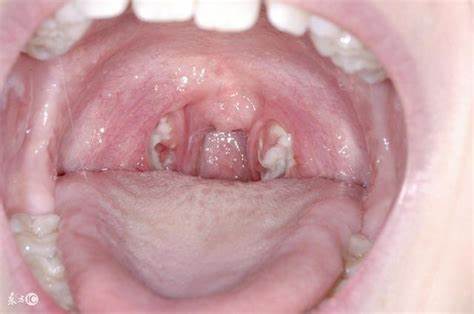

편도결석은 편도선의 작은 결석으로, 주로 치석과 세균의 축적으로 형성됩니다. 이러한 결석은 공간을 차지하고 염증을 일으킬 수 있으며, 이로 인해 구강냄새와 통증 등의 증상이 나타날 수 있습니다.

편도결석은 편도선에서 발생하는 작은 결석으로, 치석과 세균의 축적, 그리고 편도의 구조적 특성에 의해 형성됩니다. 잘못된 음식 섭취, 구강 위생의 부족, 감염 및 염증이 편도결석의 주요 원인입니다. 이를 제거하기 위해서는 면봉이나 구강 세척기를 사용하거나 가글로 결석을 제거할 수 있습니다. 또한, 음식 섭취 후 가글하거나 따뜻한 소금물로 가글 하는 등의 예방법을 실천하는 것이 중요합니다. 구강 건강을 유지하고 편도결석의 발생을 예방하기 위해 일상적인 관리와 주기적인 치과 검진을 통해 적절한 관리를 해야 합니다.